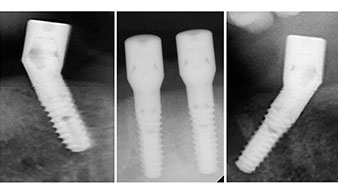

A three-dimensional cone beam computed tomography scan (CBCT, Planmeca) was performed to aid planning and minimize risks. This revealed that the quality and quantity of the available bone were sufficient for the surgery and immediate restoration using the Fast & Fixed method. Following the protocol for this concept, the implants are inserted at 35, 32, 42 and 45. Angling the distal implants by up to 45° shifts the emergence profile to posterior and generates a larger support polygon (Fig. 3).

Fast & Fixed method

Fig. 3

Angled abutments (35°) were screwed in to compensate for the divergence of the distal implants, with the result that the emergence profile of all implants was as perpendicular as possible to the bite plane. This is a prerequisite for occlusal placement of the provisional and subsequently the permanent denture (Fig. 15 and 16).

Implants

Fig. 15

Fig. 16

The light increases the contrast in the oral cavity and improves visual perception. Both the contra-angle handpiece and the S-11 straight handpiece from W&H are externally cooled, which can be seen as a great advantage because the saline solution arrives exactly where it’s needed and can also be subsequently adjusted if necessary. The contra-angle and straight handpieces can be dismantled, which is highly recommended for hygiene and sterilizability. Four SKY implants measuring 4.0 x 14mm were placed.